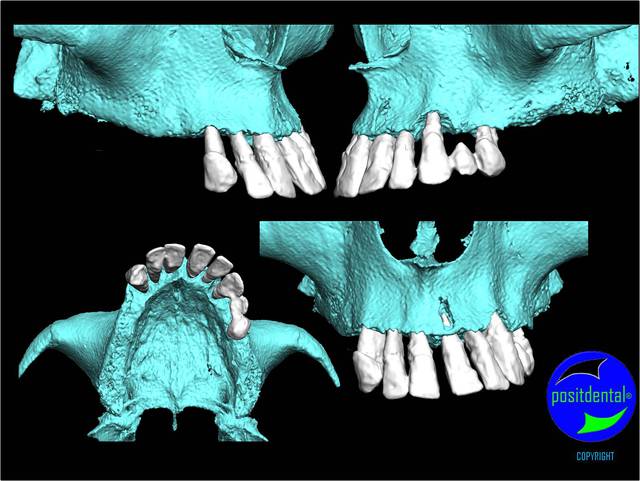

gestion des artéfacts en présence de couronnes

Wax up 3d positdental 8 kt8qmy - Eugenol

Wax up 3d positdental 9 c7cv9z - Eugenol